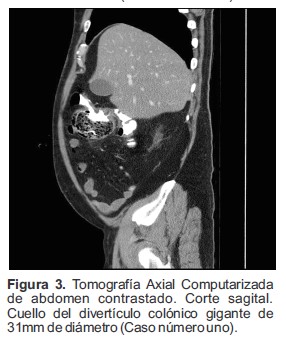

Se realizó Tomografía Axial Computarizada (TAC) de abdomen contrastado en donde se visualizó una dilatación sacular en la región del ángulo hepático del colon ascendente la cual midió 7.0 cm de diámetro antero posterior, 5.5 cm longitud y 6.2 cm transverso. Esta lesión se encontraba ocupada casi en su totalidad por materia fecal (Figura 1) y presentaba un cuello de 31.0 mm de diámetro (Figura 2 y 3), hallazgo compatible con divertículo gigante del colon, además, presentaba ligero engrosamiento de la pared y de la grasa circundante, sin embargo, no se observó gas libre en el abdomen.

Figura 3. Tomografía Axial Computarizada de abdomen contrastado. Corte sagital. Cuello del divertículo colónico gigante de 31mm de diámetro (Caso número uno).